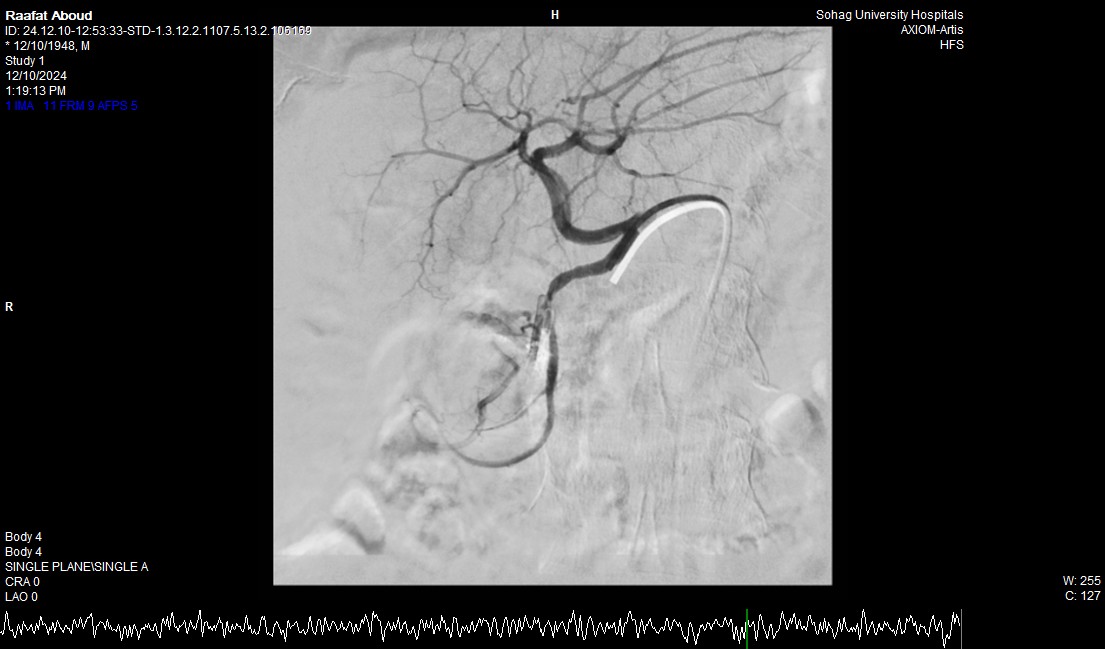

جامعة سوهاج.. أفاد الدكتور أحمد كمال، المدير التنفيذي للمستشفيات الجامعية، أن الفحوصات أظهرت وجود قرحة كبيرة في الاثني عشر وشريان نازف. نجح الفريق الطبي في التحكم بالنزيف مبدئيًا عبر تركيب مشبك معدني بالمنظار وحقن القرحة النازفة.

جامعة سوهاج.. وفي خطوة لاحقة، تم استدعاء فريق الأشعة التداخلية الذي تمكن من إغلاق الشريان النازف بشكل عاجل باستخدام جهاز القسطرة، ما ساهم في استقرار حالة المريض.

جامعة سوهاج.. أكد الدكتور محمد زاكي، رئيس قسم الأشعة، أن مثل هذه الحالات تعد من أخطر الطوارئ الطبية، حيث يتطلب التعامل معها إجراء قسطرة شريانية عاجلة لإيقاف النزيف. وأضاف أن وحدة الأشعة التداخلية مزودة بجهاز أشعة محوري متقدم مخصص لمثل هذه التدخلات، مشيرًا إلى أن هذا النجاح يعكس التعاون المثمر بين أقسام المستشفى المختلفة ووحدة الأشعة التداخلية لتقديم خدمات متميزة للمرضى.